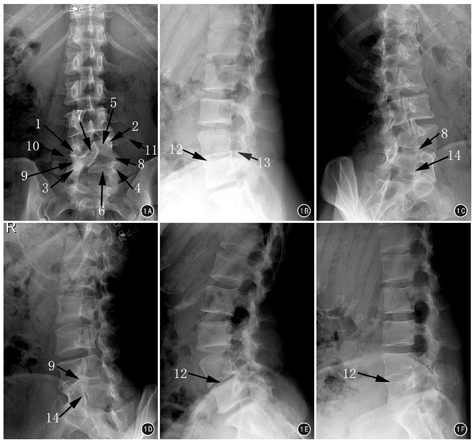

患者女,36岁,因"间断性右侧腰腿痛8年余,再次发作3个月",于2016年8月1日来海军总医院骨科就诊。曾在外院行腰椎平片及CT检查示腰骶椎隐裂(原始影像资料丢失),难以找到病痛的原因。查体:约平L4~5棘突间隙右侧压叩痛,向右下肢放射,右股神经牵拉试验阳性,右小腿内侧感觉减退,呈L4神经根受损体征。患者在我院行腰椎X线摄片检查报告示:L4~5椎间隙变窄,L5及S1隐裂。笔者阅读我院X线片,发现腰椎区域实际有以下多处形态及结构异常:正位片(图1A)示腰椎呈S形弯曲;L1~3以L2为顶椎右侧凸,似姿势性侧凸,但L3右椎板及下关节突发育肥大;右L3~4椎板间隙降至右L4椎弓根上界高度;以L4~5椎间隙为顶椎左侧凸,有多处解剖畸形。解剖畸形包括:(1)椎弓根,L4右侧椎弓根低于左侧;L4~5右侧椎间孔高度明显小于左侧。(2)横突,右侧L4横突发育小且低于左侧。(3)椎板,右侧L4及L5椎弓根向内共同发出一椎板结构,即L4~5椎板融合体,无右L4~5椎板间隙;右L4~5椎板融合体向中线上方移行,在棘突中线同左侧L4椎板融合,而左侧L5椎板游离,在中线略偏右同L4~5椎板融合体隔一左上斜向右下的裂隙,易误判为L5隐裂;右侧L4~5关节突关节辨不清。侧位片(图1B)示L4~5椎间隙变窄,L4~5椎间孔下方似有骨样突起。左斜位片(图1C)能辨出L4~5关节突关节;右斜位(图1D)示L4~5关节突关节结构消失。过伸过屈位片(图1E、图1F)示L4~5节段无活动度。腰椎CT检查及重建影像报告仅提及腰骶椎隐裂。笔者阅读CT横断面图像,未见到L3~S1节段有椎间盘突出;但对L4~5椎间隙节段的横断面连续CT图像观察发现L4~5右侧椎间孔前后径变小,自L5椎体右后缘有骨性隆起使椎间孔呈迂曲状,右侧L4~5椎板融合体宽度明显为厚(图2)。矢状位CT重建见右侧L4~5椎间孔周径明显变小,L4~5关节突关节融合(图3)。冠状位CT重建图像证实右L4~5关节突关节融合,右侧L4椎弓根平面下降,右侧L4横突发育不良,右侧L4~5椎板融合(图4)。患者经卧床休息、脱水及激素冲击治疗,右侧下肢放射痛减轻。建议行腰椎MR或腰椎管造影了解神经根走行有无异常,患者因症状缓解拒绝再行进一步检查。随访3个月,期间右侧下肢放射痛复发1次,但未达到3个月前强度,口服镇痛消肿药物及卧床休息后,症状再次好转。患者暂未手术,继续随访观察中。